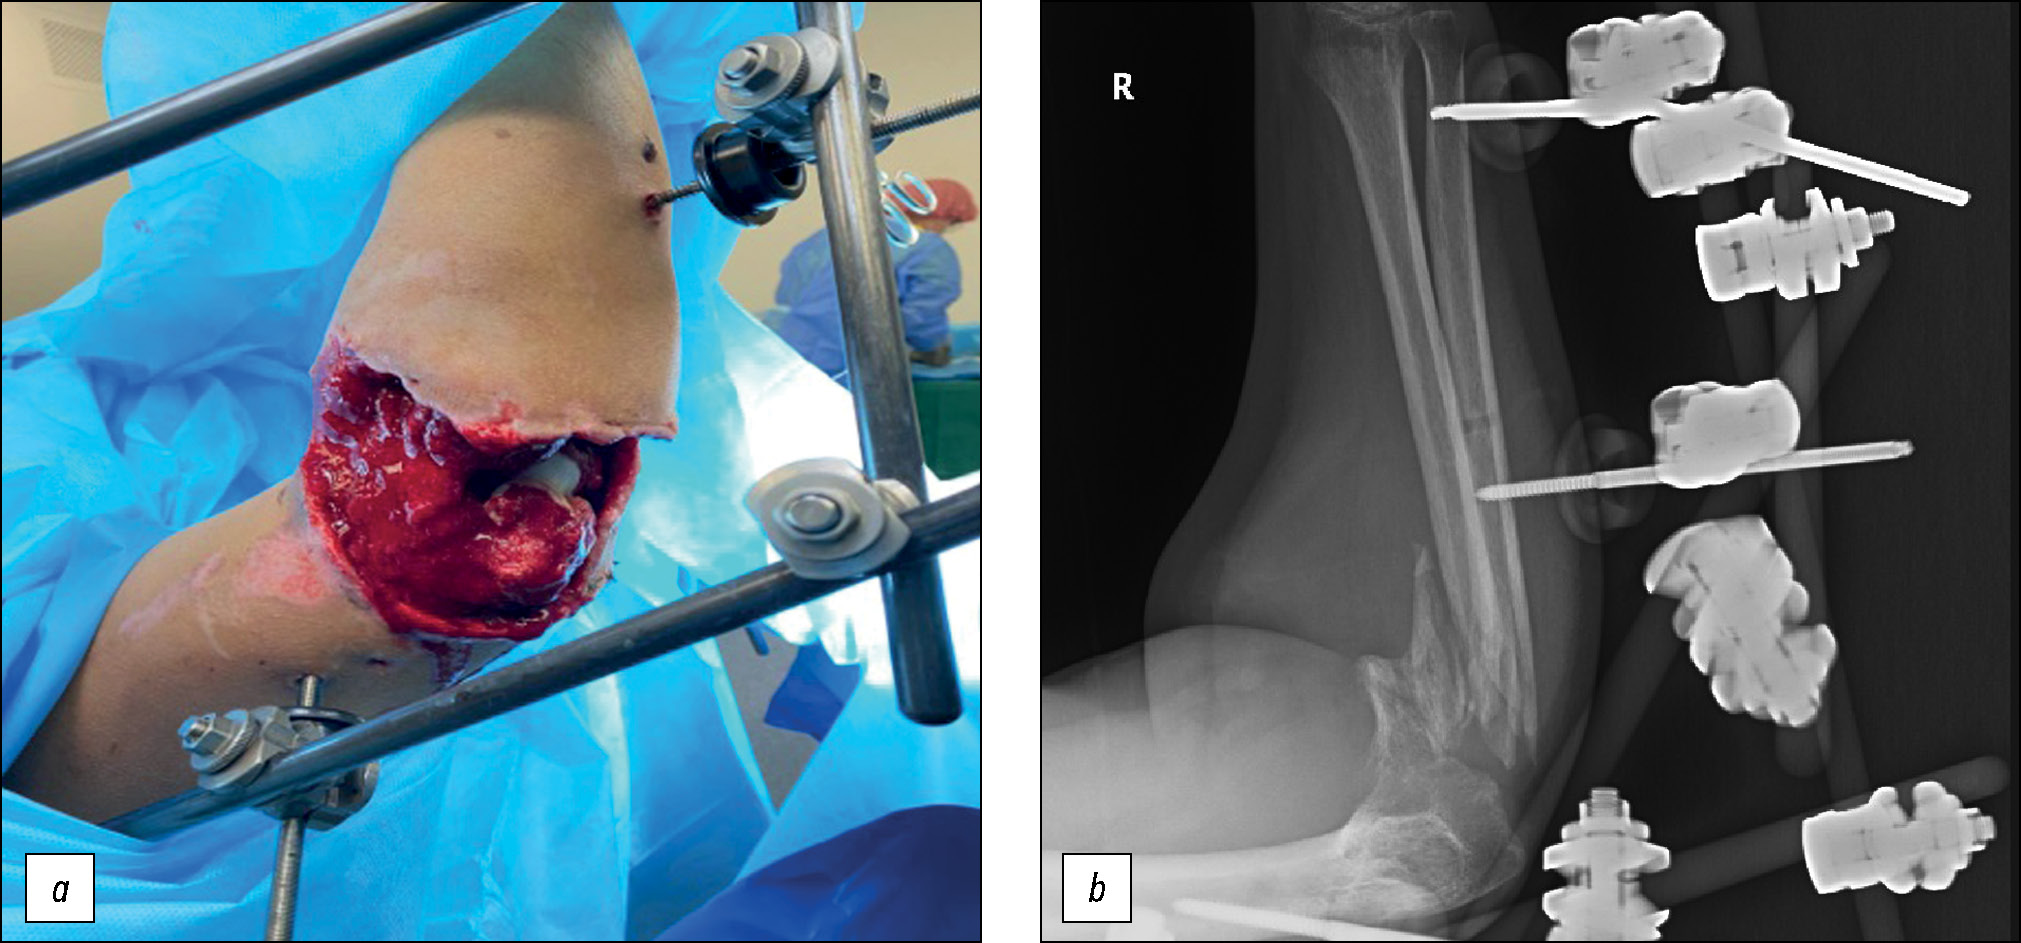

Пациенты при поступлении были обследованы с применением клинических, лабораторных и инструментальных методов исследования. Всем больным выполнялась первичная или повторная первичная хирургическая обработка ран (рис. 1), которая включала взятие бактериального посева для определения микрофлоры и чувствительности к антибактериальным препаратам, радикальный дебридмент с удалением свободно лежащих костных отломков вне зависимости от их размера, фиксацию отломков аппаратом внешней фиксации — комплектом стержневым военно-полевым «плечо — предплечье — кисть». При нестабильной фиксации, выполненной на ранних этапах оказания медицинской помощи, проводили дополнительные стержни Шанца для минимизации подвижности отломков. По показаниям выполняли фасциотомию.

Рис. 1. Оценка состояния мягких тканей при поступлении пациента в стационар.

Fig. 1. Assessment of the condition of the soft tissues upon admission of the patient to the hospital.

Военнослужащий Д., 25 лет. Из анамнеза и представленной медицинской документации известно, что во время выполнения боевой задачи пациент получил осколочное ранение области правого локтевого сустава. Первая помощь оказана на месте. В первые сутки после ранения выполнена первичная хирургическая обработка, наложен стержневой аппарат внешней фиксации КСТ, проведена медикаментозная терапия. На 10-е сутки после ранения пациент доставлен авиатранспортом в ФГБУ «Главный военный клинический госпиталь им. Н.Н. Бурденко» Минобороны России. По результатам осмотра и обследования установлен диагноз: осколочное сквозное проникающее ранение правого локтевого сустава с внутрисуставным оскольчатым переломом проксимальных метаэпифизов обеих костей предплечья с дефектом костной ткани. Посттравматическая невропатия локтевого и лучевого нервов (рис. 11).

Рис. 11. Пациент Д.: а — внешний вид раны при поступлении, b — рентгенограммы при поступлении.

Fig. 11. Patient D.: a — appearance of the wound upon admission, b — radiographs upon admission.

При первичном осмотре определялась рана по задне-наружной поверхности правого локтевого сустава размерами 18×8 см, занимающая 2/3 диаметра поверхности локтевого сустава, дном раны являлись мышцы, свободнолежащие костные отломки, определялось серозное отделяемое. Сразу при поступлении взят бактериальный посев из раны для определения микрофлоры и чувствительности к антибактериальным препаратам. Пациенту проводилось лечение в объёме перемонтажа аппарата внешней фиксации предплечья, выполнялись повторные хирургические обработки с использованием физических методов лечения (гидромеханическое очищение раны при помощи аппарата Pulse Vac, ультразвуковая кавитация, лазер). Далее применялся метод вакуумной терапии раны (VАС) в режиме постоянной вакуумной аспирации. Медикаментозная терапия включала анальгетики, эмпирическую схему антибактериальной терапии широкого спектра действия при поступлении (цефоперазон/сульбактам 1 г + 1 г 2 раза в день в/в капельно + метронидазол 500 мг 3 раза в день в/в капельно), на 7-е сутки произведена смена антибактериальной терапии на линезолид 600 мг 2 раза в день согласно полученному бактериологическому посеву. Достигнуто заживление раны первичным натяжением на 25-е сутки после ранения (рис. 12).